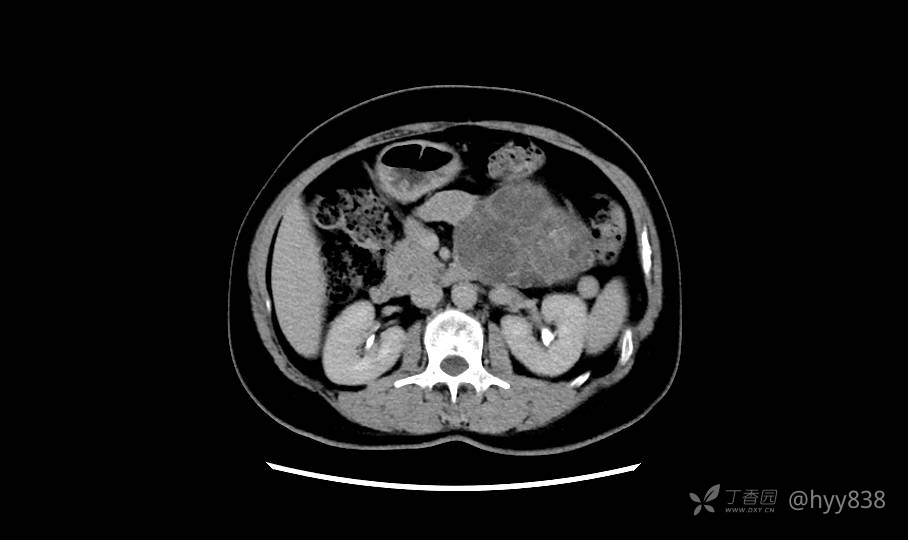

静脉期(机器故障---延迟期了)